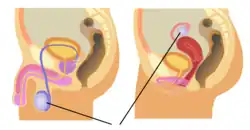

Reproductive system

The purpose of the reproductive system is to reproduce and nurture the growth of offspring. The functions include the production of germ cells and hormones.[39] The sex organs of the male reproductive system and the female reproductive system develops and mature at puberty. These systems include the internal and external genitalia.

Female puberty generally occurs between the ages of 9 and 13 and is characterized by ovulation and menstruation; the growth of secondary sex characteristics, such as growth of pubic and underarm hair, breast, uterine and vaginal growth, widening hips and increased height and weight, also occur during puberty.[40] Male puberty sees the further development of the penis and testicles.[41]

The female inner sex organs are the two ovaries, their fallopian tubes, the uterus, and the cervix. At birth there are about 70,000 immature egg cells that degenerate until at puberty there are around 40,000. No more egg cells are produced. Hormones stimulate the beginning of menstruation, and the ongoing menstrual cycles.[40][42] The female external sex organs are the vulva (labia, clitoris, and vestibule).[43][40]

The male external genitalia include the penis and scrotum that contains the testicles. The testicles are gonads that produce the sperm cells which are ejaculated in semen through the penis. Unlike the egg cells in the female, sperm cells are produced throughout life. Other internal sex organs are the epididymides, vasa deferentia, and some accessory glands.